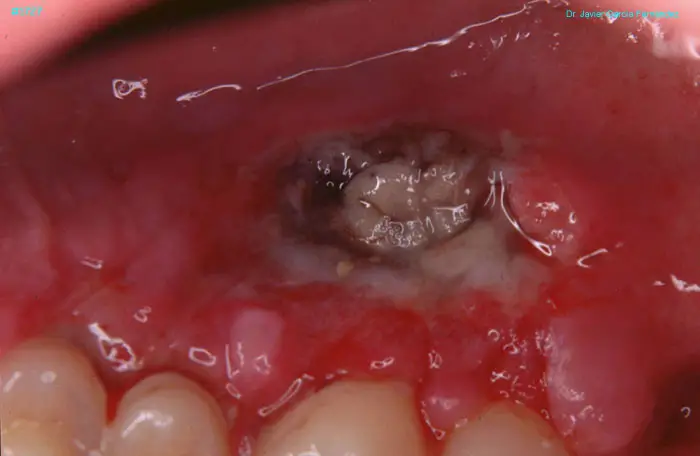

Atlas of Surgical Techniques in Periodontics. Chapter IV. Atlas de Técnicas Quirúrgica en Periodoncia

image 235